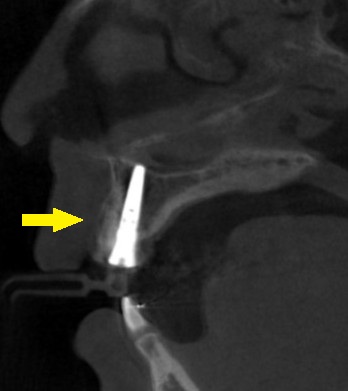

抜歯して、インプラントが良いのではないかと説明させていただき、了承していただけました。

まずは抜歯し、歯肉の治癒を2か月待って、インプラント埋入と同時に、骨のなくなった唇側に人工骨を補填して、骨造成を行いました(下の写真下段右)。